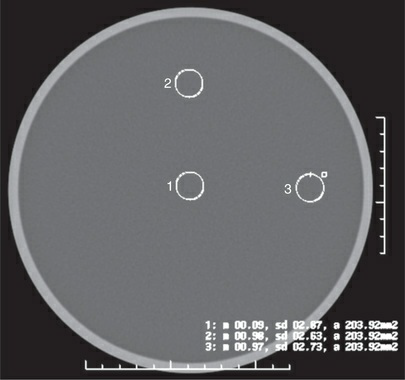

Which of the following components of CT image quality are

being evaluated in the figure?

1. low-contrast detectability

2. noise

3. uniformity

a. 2 only

b. 1 and 2 only

c. 1 and 3 only

d. 2 and 3 only

2 and 3 only

Which region of interest (ROI) on the figure demonstrates the

greatest amount of image noise?

a. 1

b. 2

c. 3

d. impossible to determine from the information provided

1